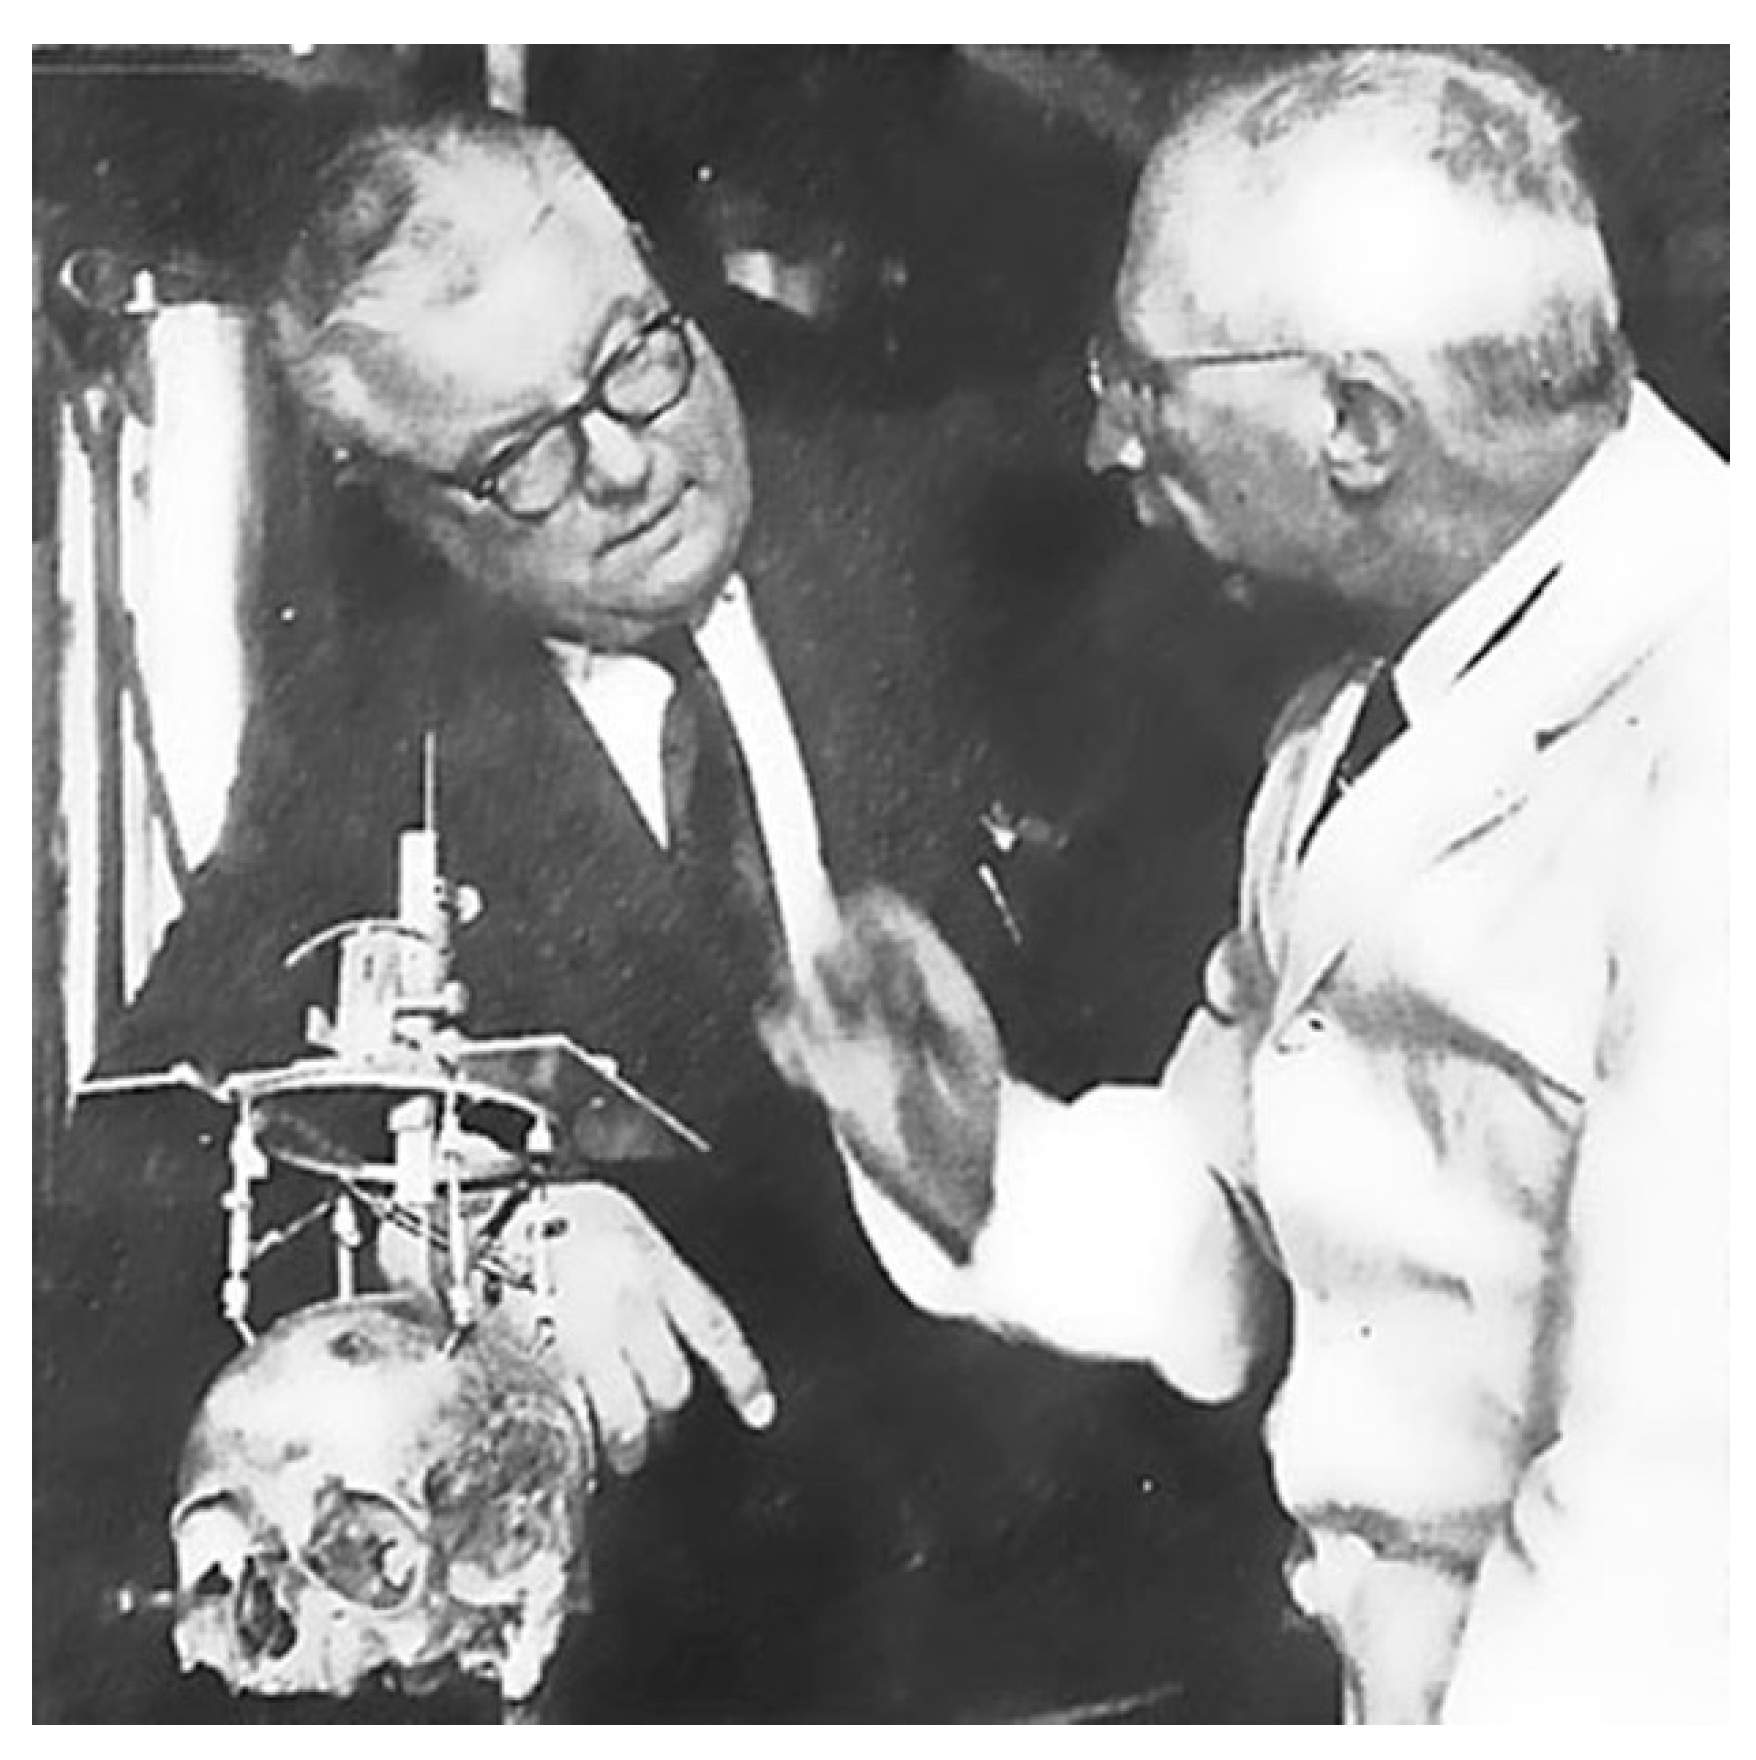

3. The Invention of the Stereotactic Atlas

- Spiegel, E.; Wycis, H. Stereoencephalotomy, Thalamotomy and Related Procedures. I. Methods and Stereotaxic Atlas of the Human Brain; Grune and Stratton: New York, NY, USA, 1952. [Google Scholar]

- Spiegel, E.; Wycis, H. Stereoencephalotomy. II. Clinical and Physiological Applications; Grune and Stratton: New York, NY, USA, 1962. [Google Scholar]